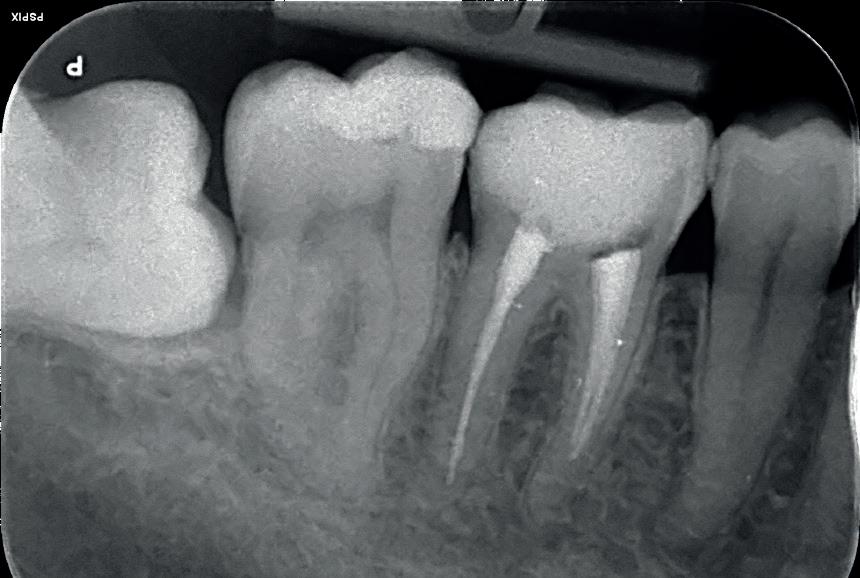

When treating odontogenic infections, clinicians must exercise caution to prevent the spread of infection. For example, when conducting root canal treatment (RCT), dentists should eliminate the source of infection; make incisions on healthy skin or mucosa; not damage vital structures during exploratory dissection; irrigate copiously; and provide adequate drainage to keep the abscess cavity open.v The use of a rubber dam is also highly recommended to further reduce the risk of infection during endodontic treatment.

truly maximised when the right technology and materials are introduced to the practice. This means finding a supplier you can trust to consistently deliver high-quality products and on-going services. The only provider to offer a comprehensive digital 3D printing ecosystem designed specifically for dentists, SprintRay recently launched a brand-new ceramic solution that is one-of-a-kind. The SprintRay Ceramic Crown features high strength, excellent margin fit and radiopacity. Combine this and the SprintRay Pro 3D Printer for maximum workflow efficiency –crowns can be printed in just 10 minutes, for a total treatment time of 45 minutes or under.